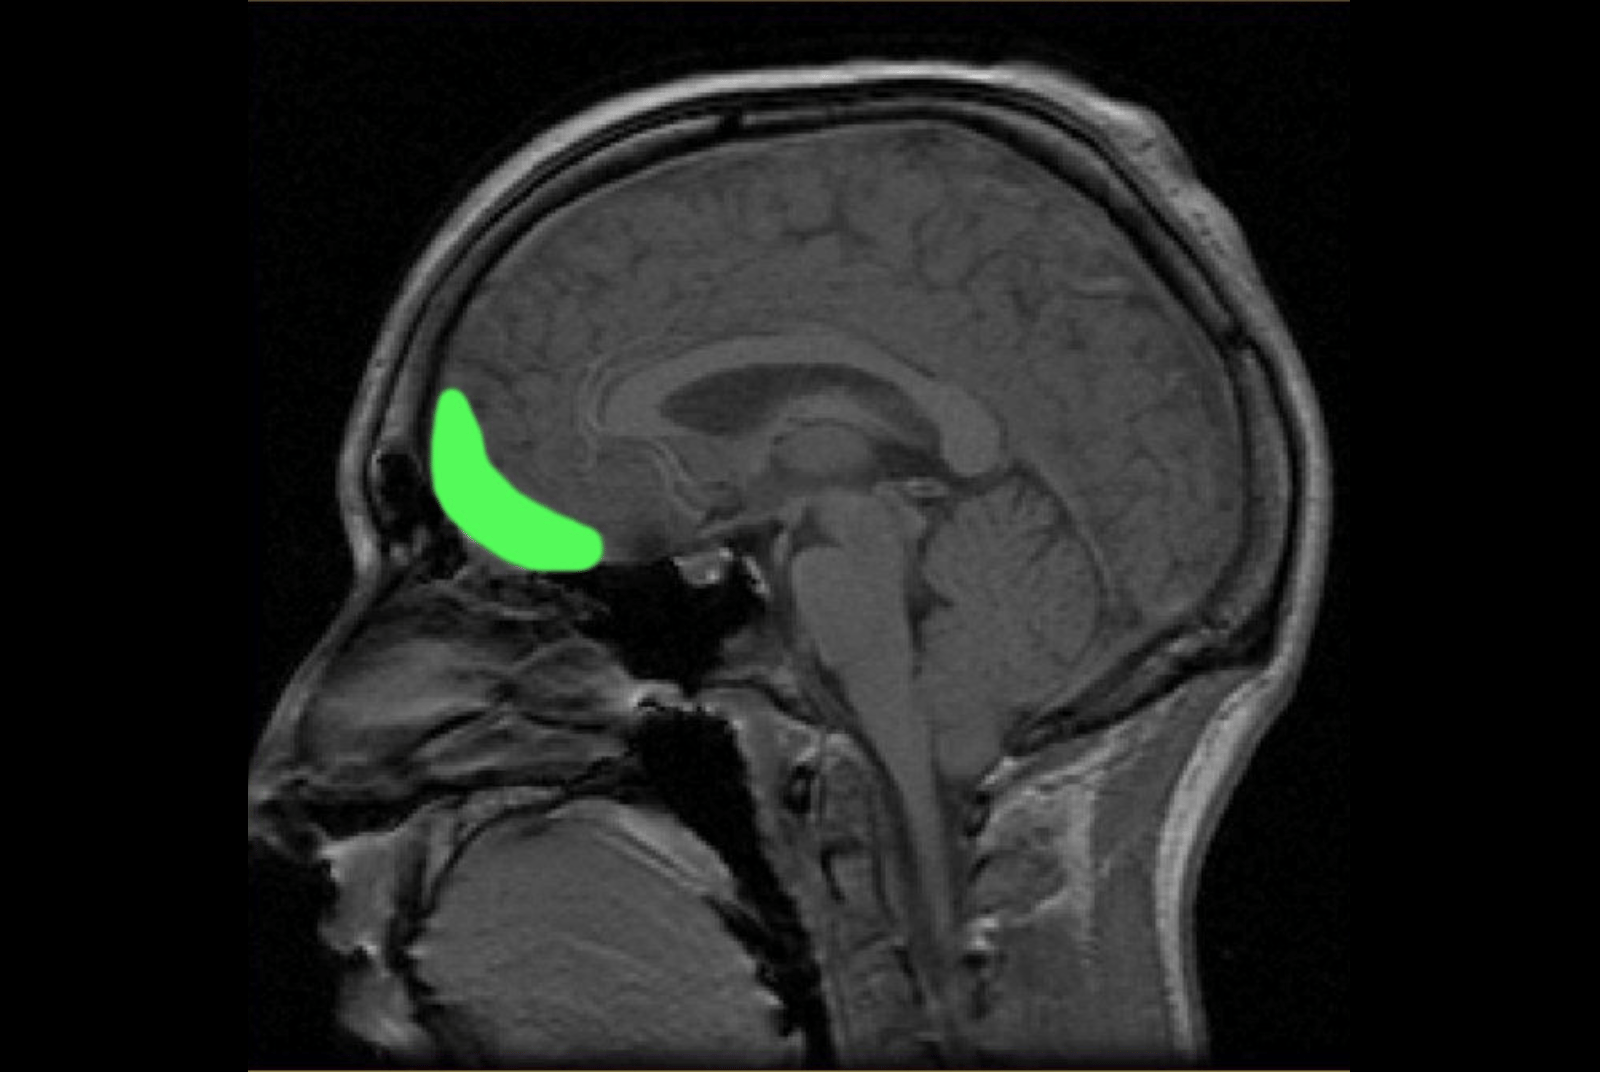

圖中綠色處,為眼窩額葉皮質的所在位置。

在三個不同的研究中,腦掃描器裡的受試者交替給某個東西的美(好比說臉)或某個行為的善做出評分。這兩類評價都活化了同一個區域——眼窩額葉皮質(orbitofrontal cortex,OFC),越是美或善,眼窩額葉皮質就越活化(而腦島就越不活化)。